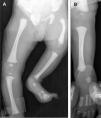

Se realiza estudio radiológico de extremidades inferiores que demuestra una deficiencia focal de fémur proximal izquierdo junto con ausencia de peroné y del quinto dedo; no se observa el núcleo de osificación tibial (fig. 1). El resto del mapa óseo no muestra otras alteraciones. Se lleva a cabo ecografía de caderas en la que se aprecia la cabeza femoral izquierda displásica con normalidad de acetábulos, y ecografía renal, cuyo resultado es normal.

Figura 1. A) Fémur corto y curvado.B)Ausencia de peroné ipsolateral.